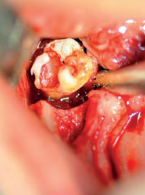

Powikłania związane z zatrzymaniem zębów stałych

Complication of permanent teeth impaction

Mansur Rahnama, Michał Łobacz, Wojciech Popowski, Klaudia Masłowska, Katarzyna Wieczorek

Retentio dentis jako problem kliniczny w codziennej praktyce lekarza pedodonty. Opis przypadku

Zobacz więcej

Retentio dentis as a clinical problem in daily practice of a pedodontist – a case report

Katarzyna Zaborowicz, Agata Daktera‑Micker, Aneta Olszewska, Katarzyna Cieślińska, Barbara Biedziak